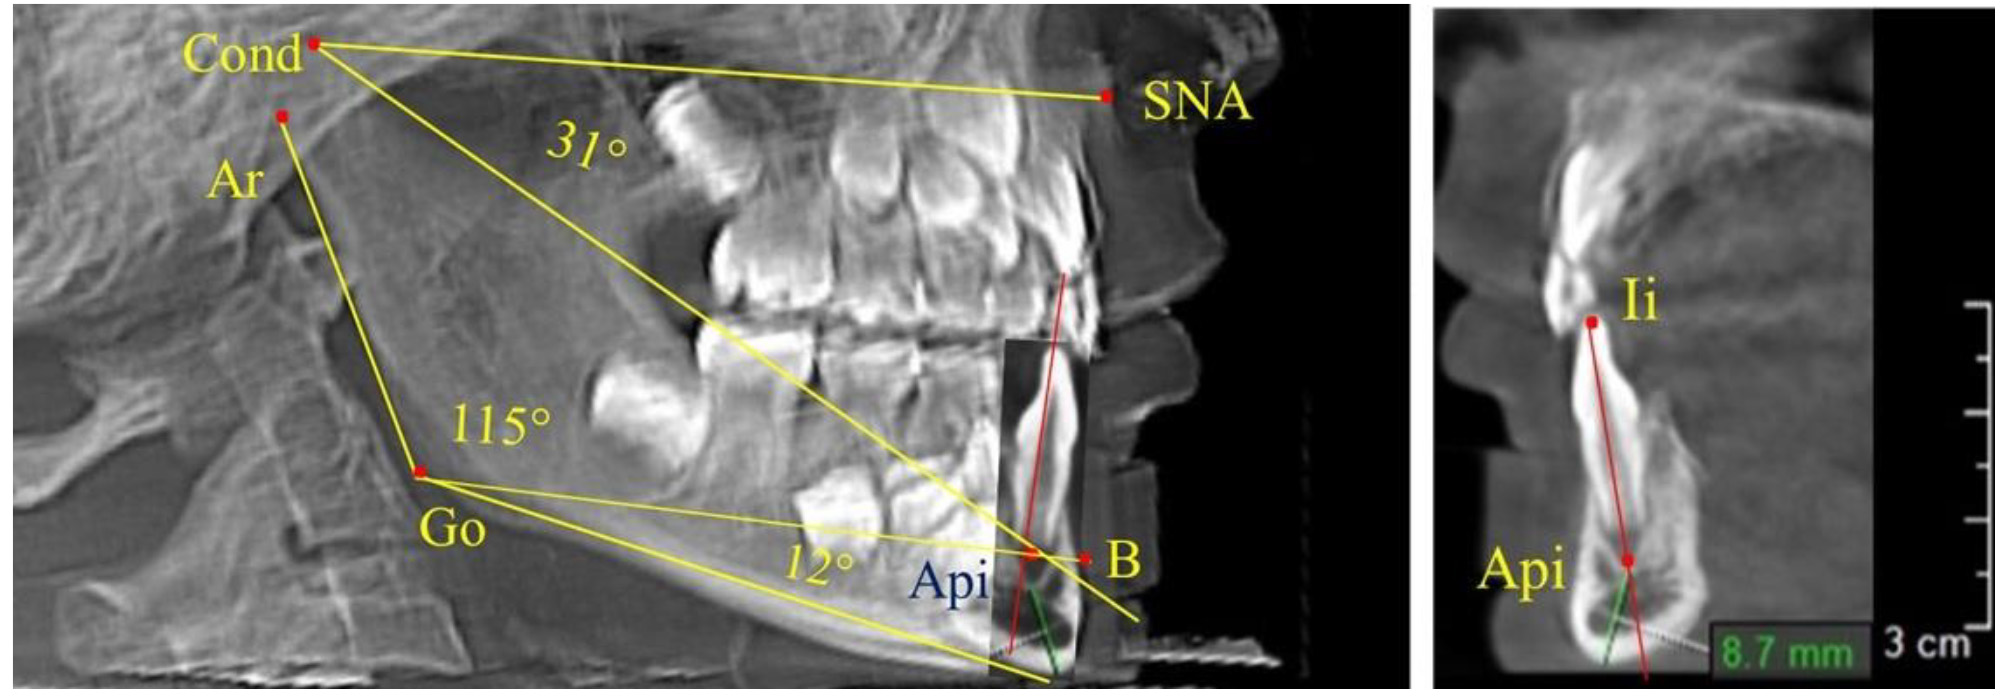

После смены всех молочных зубов (анализ 9 ТРГ) и после прорезывания вторых постоянных моляров (7 человек) происходил очередной этап подъема высоты прикуса с увеличением размеров костей гнатической части лица. Однако величина основного угла гнатической части лица SNA-Cond-Api, так же как в молочном и сменном прикусе, в норме составляла (30,02 ± 1,25)°, что не имело достоверных различий (р ˃ 0,05) с аналогичным параметром, анализируемом в других группах исследования. Угол нижней челюсти и его составляющие отличались вариабельностью параметров при различных показателях нижнечелюстного угла (рис. 6).

Рис. 6. Варианты 3D рентгенограмм детей после смены всех молочных зубов (а) и после прорезывания вторых моляров (б)

Таким образом, данные, полученные при исследовании детей с физиологическим прикусом в различные периоды онтогенеза, показали, что величина основного угла гнатической части лица SNA-Cond-Api была относительно стабильным параметром, вне зависимости от линейных параметров челюстных костей. Данный показатель может служить ориентиром для дифференциальной диагностики зубоальвеолярных и гнатических форм аномалий окклюзии в вертикальном направлении.